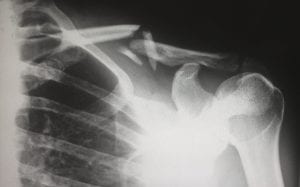

X-ray showing a broken clavicle; image by Harlie Raethel, via unsplash.com.sX-ray showing a broken clavicle; image by Harlie Raethel, via unsplash.com.s

Personal injury however is not covered as part of your vehicle’s insurance and it is up to the injured party to pursue that separately. To do that they would normally employ the services of a personal injury attorney in Vancouver BC who would attempt to pursue the other party and personal injury claims can be made if your injury has been caused by another person’s negligence. A personal injury lawyer will require details of your injury and will then pursue a financial settlement on your behalf.